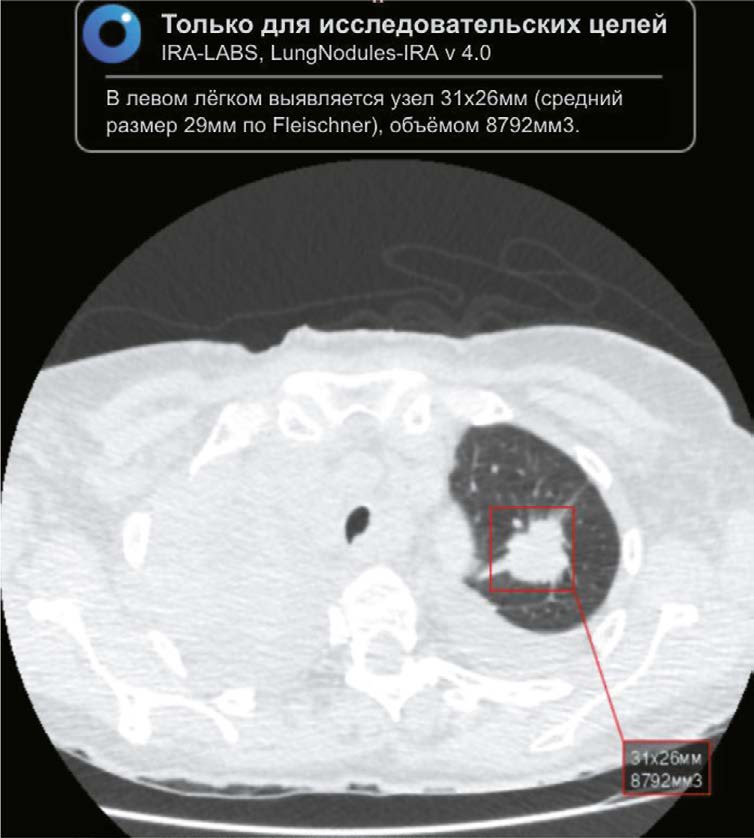

Цель — оценка возможности использования алгоритма искусственного интеллекта, направленного на поиск лёгочных узлов по данным компьютерной томографии органов грудной клетки, полученным в период пандемии COVID-19, для выявления рака лёгкого.

Материалы и методы. В ретроспективное исследование вошли результаты компьютерной томографии органов грудной клетки пациентов из Красноярского края с диагнозом COVID-19 из PACS-архива, выполненные в период с 01.11.2020 по 28.02.2021. Интервал времени между проведёнными компьютерными томографиями и применением алгоритма искусственного интеллекта составил от двух лет и одного месяца до двух лет и пяти месяцев. Использовали алгоритм искусственного интеллекта Chest-IRA. Он выявлял лёгочные узлы объёмом более 100 мм3. Рентгенологи разделили результаты на три группы в зависимости от вероятности рака лёгкого. Оценка экономической выгоды применения алгоритма учитывала затраты на заработную плату и экономию на лечении ранних стадий рака лёгкого, влияющую на валовой региональный продукт.

Результаты. Из 10 500 результатов компьютерной томографии, алгоритм искусственного интеллекта выявил узловые образования в 484 случаях. Определены 192 пациента с высокой вероятностью рака лёгкого, 103 — без признаков и 60 — с неубедительными признаками. 112 пациентов с высокой и средней вероятностью рака лёгкого не обращались за медицинской помощью. Применение искусственного интеллекта позволило подтвердить 100 (28,2%) гистологически верифицированных случаев рака лёгкого, при этом I–II стадия выявлена в 35%.

Заключение. Использование искусственного интеллекта для анализа результатов компьютерной томографии органов грудной клетки демонстрирует высокую эффективность в отношении выявления узловых образований лёгких, в том числе на фоне COVID-19, что подтверждает перспективы его применения для раннего обнаружения случайных лёгочных узлов, которые могли бы быть пропущены.